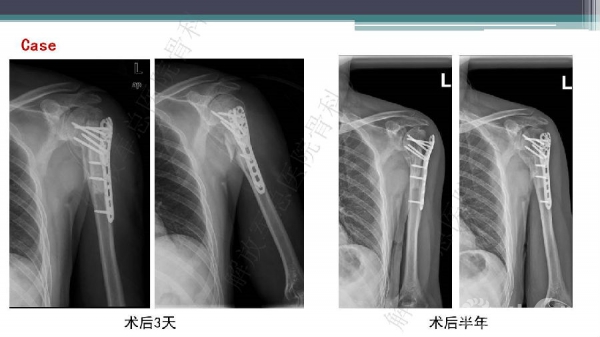

导 语:肱骨近端骨折仍是最常见的骨科损伤之一,尤其好发于老年人群。移位型肱骨近端骨折通常需要手术治疗,但是由于骨折粉碎、骨质较差,手术治疗往往会比较困难。随着锁定钢板的发明,使得并发症显著降低。但仍存在一些问题,对于内侧皮质不连续缺乏内侧可靠支撑,合并老年骨质疏松的病人,锁定钢板吊臂样结构就无法满足力学要求,随着康复锻炼可能出现断板、断钉、螺钉切出肱骨头等并发症。本期解放军总医院骨科专家们对老年肱骨近端骨折的问题与创新手术技术进行了详细讲解。